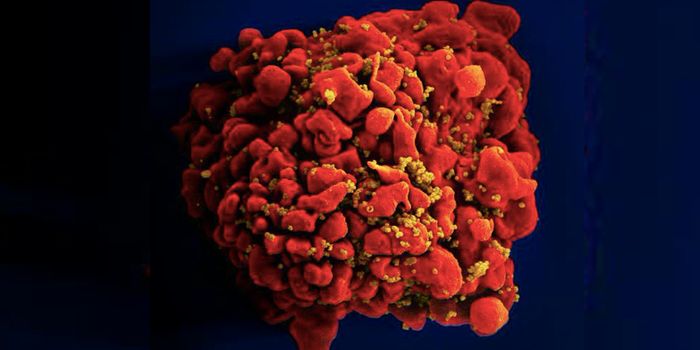

FEB 21, 2022Cell & Molecular BiologyTwo people have been cured of HIV, and now, a US woman joins them. In this third case, stem cell transplants were being ...

NOV 30, 2021ImmunologyHIV is a master of disguise. Once the virus enters the body, it has a number of sophisticated mechanisms through which i ...

NOV 22, 2021MicrobiologyThough treatments are available, there is no cure or vaccine from HIV, which impacts about 38 million people worldwide. ...

SEP 06, 2021MicrobiologyHIV vaccines have remained elusive in part because the virus has a powerful ability to mutate, and there are so many str ...

JUN 24, 2021ImmunologyA new study has revealed how stem cells can be used to amplify immune responses to HIV, the virus that causes AIDS. The ...